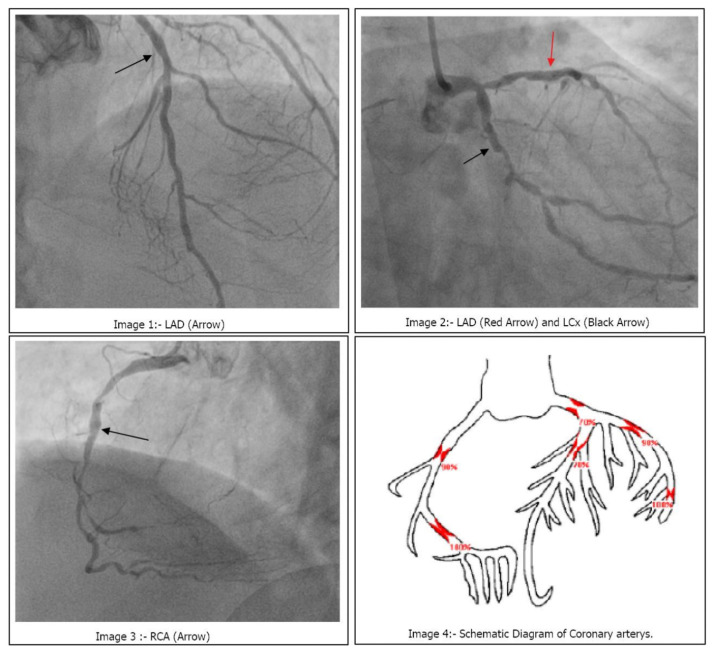

Case presentation: A 64-year-old male with a medical history of hypertension, HIV, and opioid dependence presented with chest pain and dyspnea. The patient's ECG showed changes suggestive of an inferior myocardial infarction. During a dobutamine stress test, the patient developed VF and was successfully resuscitated. Subsequent coronary angiography revealed severe triple vessel disease, and the patient underwent coronary artery bypass surgery. He recovered well postoperatively and was discharged on dual antiplatelet therapy.